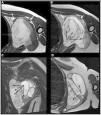

Synovial sarcoma (SS) is a rare malignant neoplasm of the soft tissue adjacent to joints. It is the most commonly diagnosed non-rhabdomyosarcoma soft-tissue sarcoma (STS) in childhood (30%). Its most frequent location is the knee and ankle, and it is the most common STS to affect the foot. Unlike other STS, it has slow growth and an earlier age at diagnosis (adolescents and young adults), which is why many cases are initially misdiagnosed as benign processes. Magnetic resonance imaging (MRI) is key due to its characterisation capabilities as SS shares features with other STS. Definitive diagnosis is achieved through a pathological study that shows the pathognomonic translocation t(x;18)(p11;q11) with the fluorescence in situ hybridisation (FISH) technique. The objective of this article is to highlight the key characteristics that are useful for diagnosing SS, fundamentally through the use of radiological imaging techniques, as well as nuclear medicine and pathological studies, illustrated with cases diagnosed in our centre.